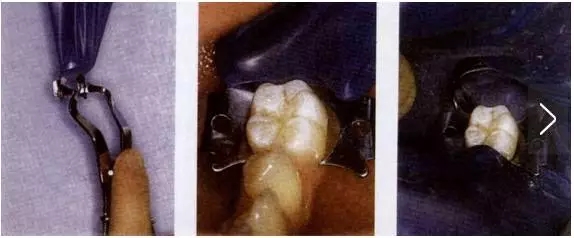

1、翼法(wing technique)

在口外用橡皮障支架撐開打好孔的橡皮布,將橡皮障夾的翼穿過(guò)橡皮布的孔并用橡皮障夾鉗撐開,將橡皮障夾和橡皮布一同安放到需要隔離牙齒的頸部。

橡皮障夾的喙應(yīng)位于牙齒的外形高點(diǎn)下方,與牙齒有四點(diǎn)接觸,否則橡皮障夾容易轉(zhuǎn)動(dòng)和滑脫。

此法為口內(nèi)內(nèi)操作時(shí)間最短的一種方法,因此最為常用。